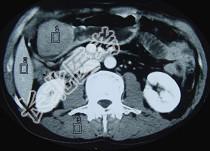

- 单项选择题女性,42岁, 腹痛、黑便1周,CT扫描见胃窦部圆形块影, 最佳的诊断是  (    )